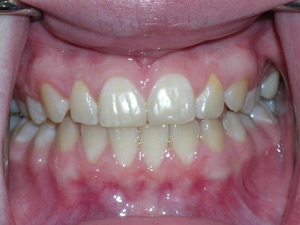

Here’s a fascinating case of a young lady who had a completely blocked out premolar.

With a combination of braces, expansion and trimming we were able to bring it in. Watch!

Here are the results.